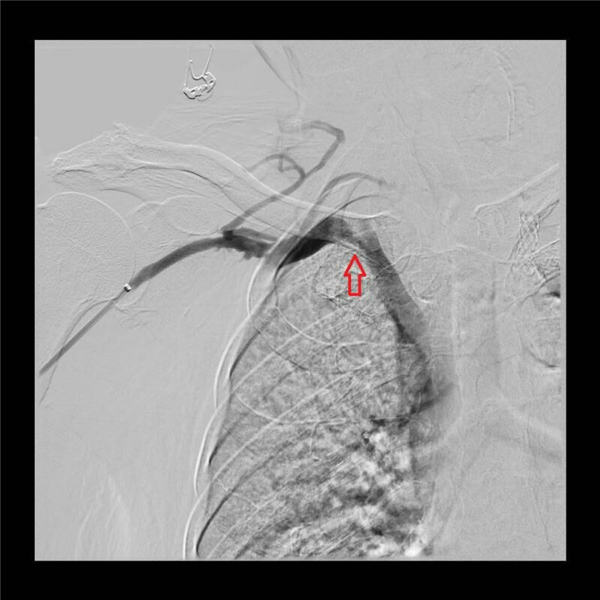

最后,再次造影,发现三处血管狭窄基本消失,血液顺畅回流到上腔静脉(如下图)。